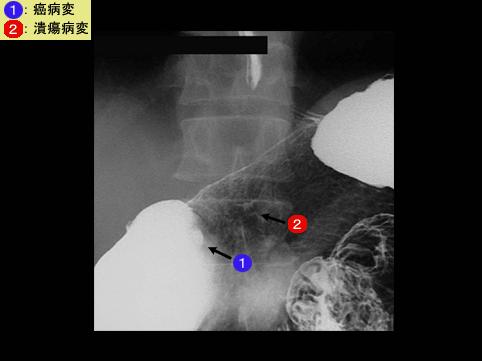

clasificación del pacienteTumor Epitelial Maligno/Cáncer a células en Sello de Anillo

parte(separada por órganos)estómago(región)/ángulo

método de exámenRayos X

clasificación ectoscópica de tumoresTipo 0(tipo superficial)/Tipo III(III+IIc)

diámetro mayor del tumor10 - 14

grado de penetraciónsm